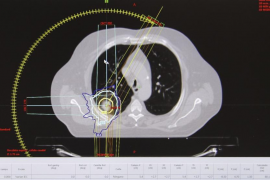

Son Espases incorpora una tècnica per administrar dosis més altes de radiació als tumors

El Servei d'Oncologia Radioteràpica de l'Hospital Universitari Son Espases...